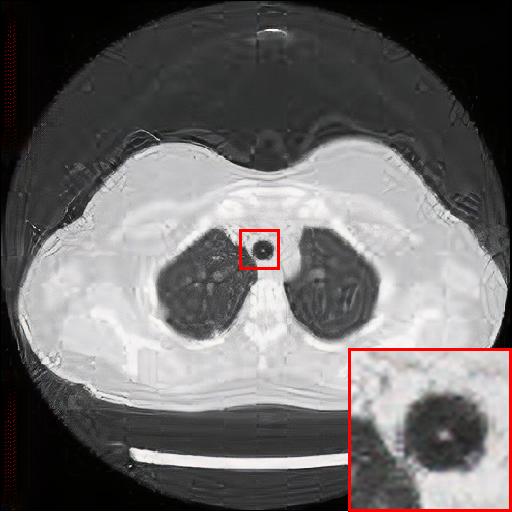

Refer to caption

(a) Original HD image

(b) Bicubic

(c) EDSR

(d) WDSR

(e) T-GAN

Figure 5: Reconstruction results of each algorithm for low-doze chest CT images.

In this section, we selected chest CT images of COVID-19 patients in an actual hospital [26] for our experiments. The visualization results of the experiments are shown in Figure 5 and Figure 6. The experimental results show that our proposed T-GAN is also applicable to the super-resolution reconstruction of low-dose CT images, and the high-resolution images obtained by our model have more detailed information compared with the baseline algorithm.